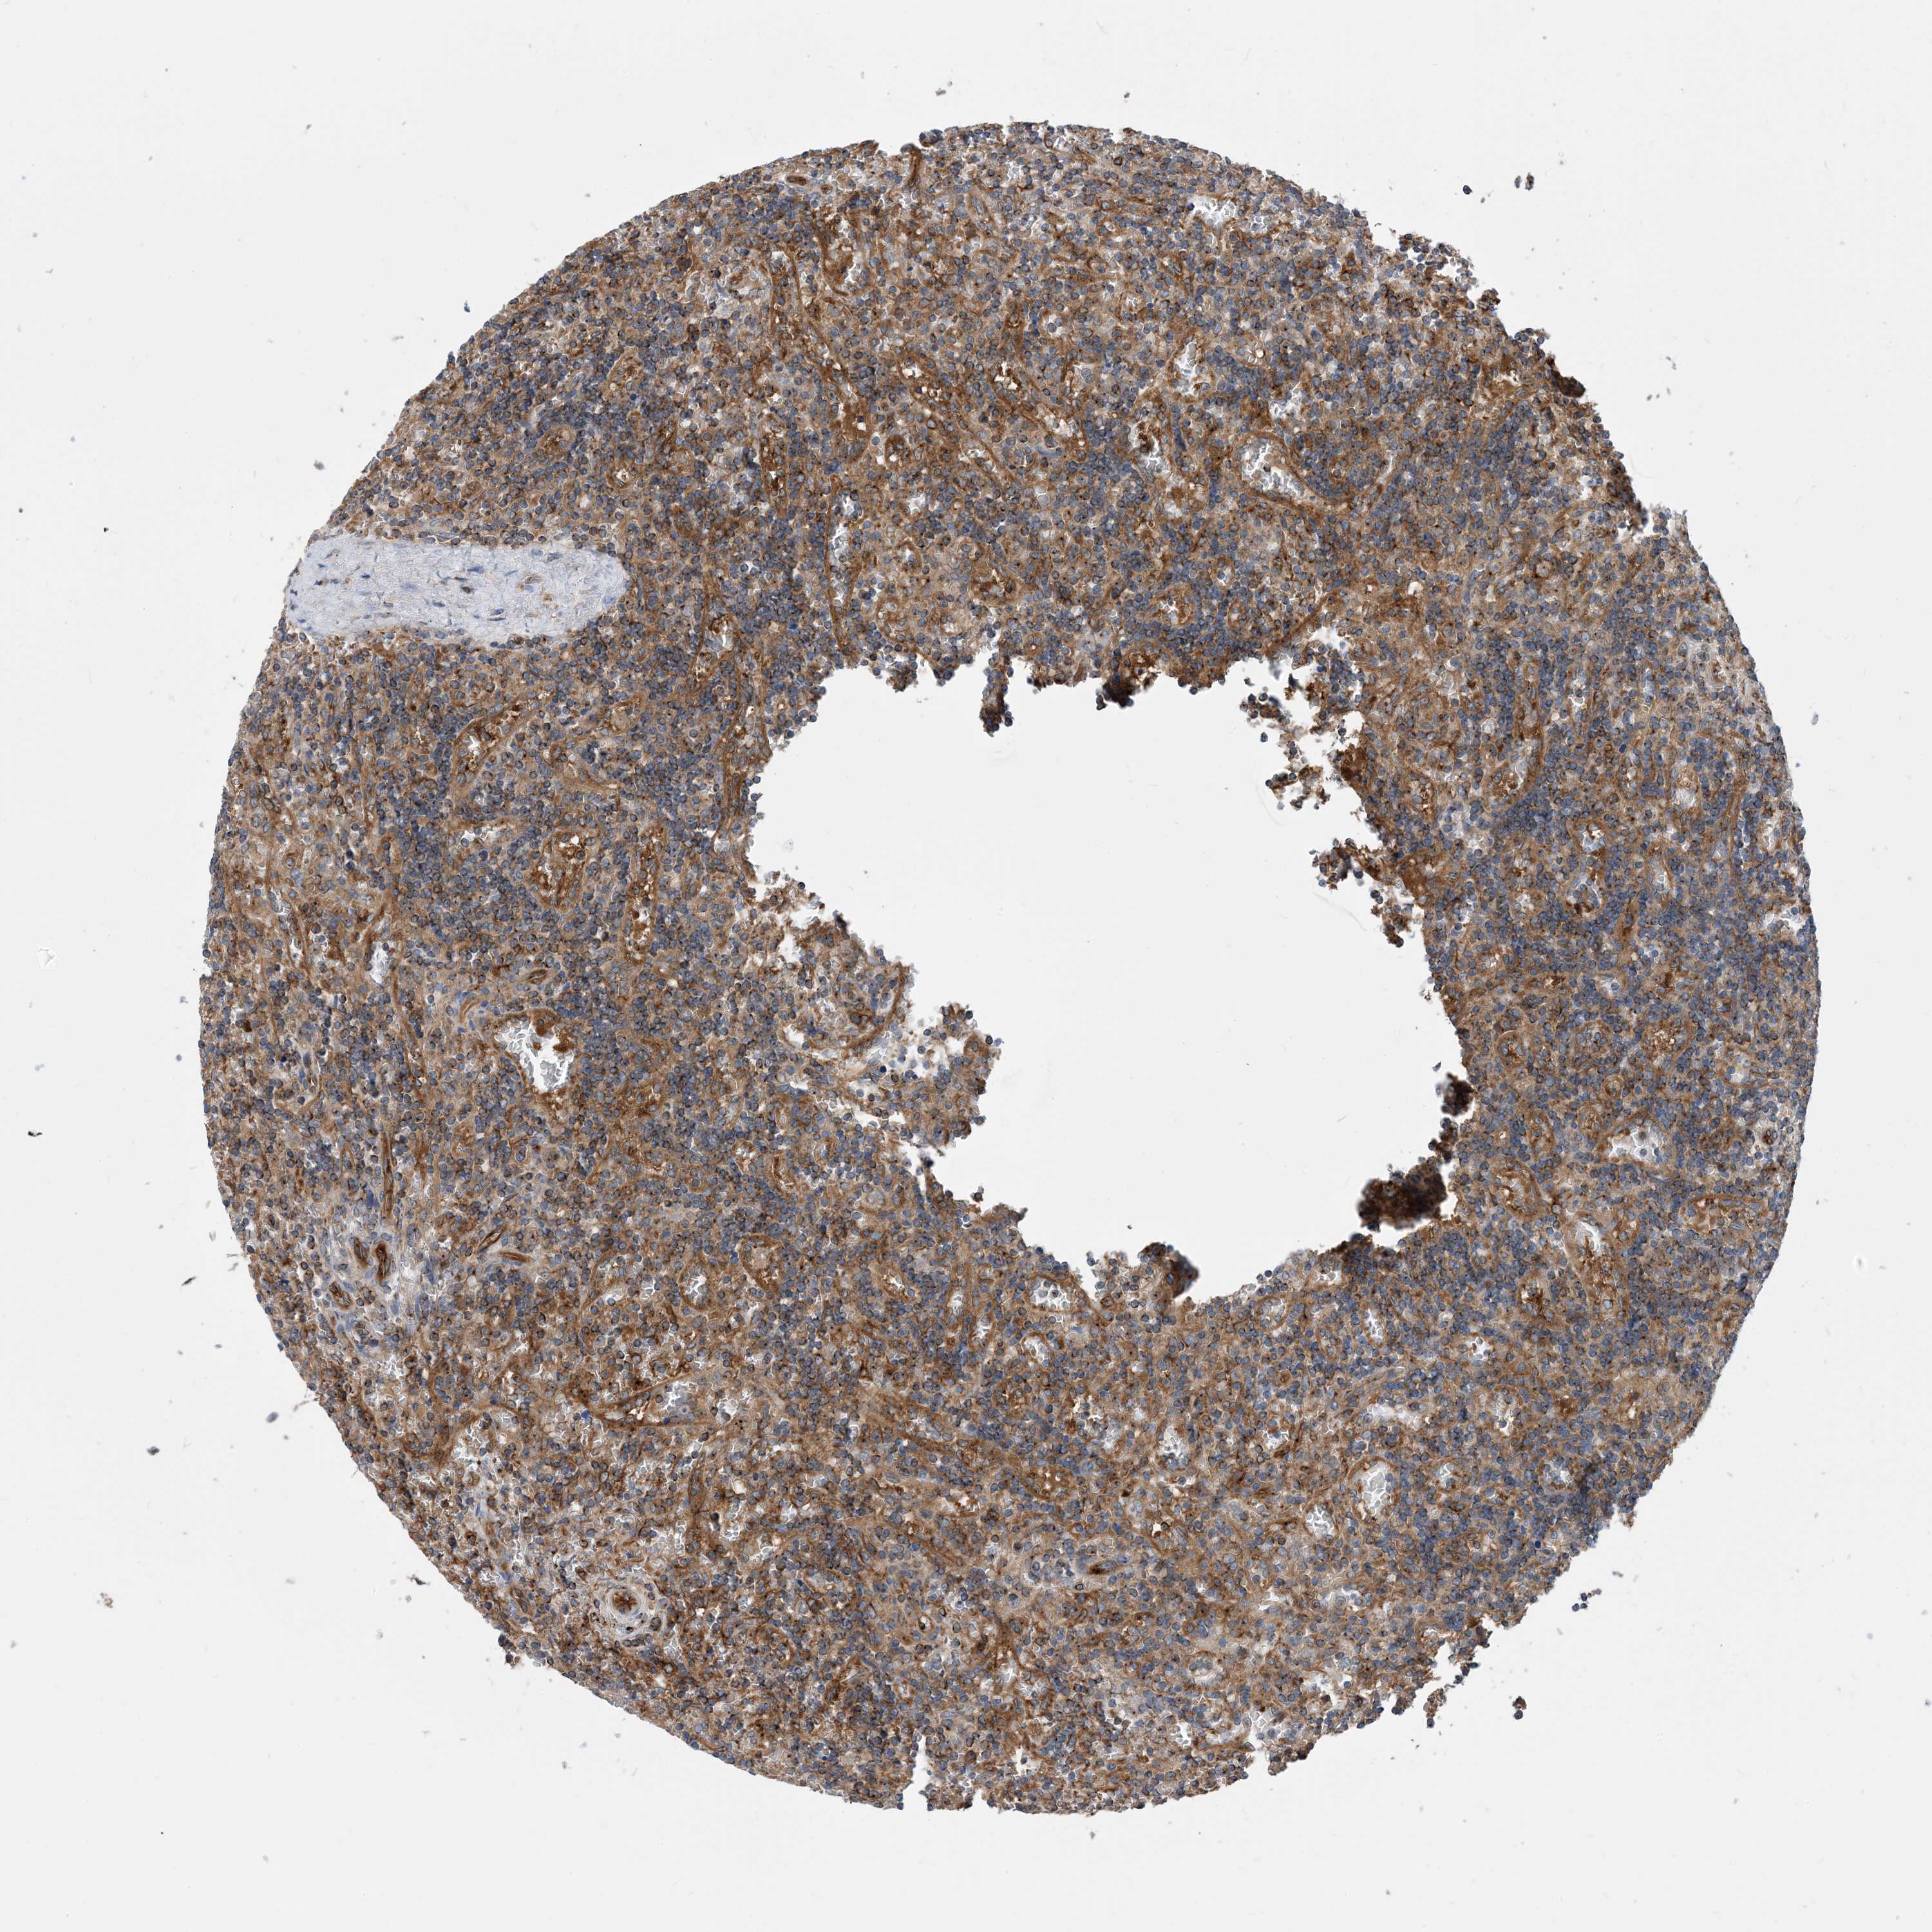

CANCER LYMPHOMA Show tissue menu

LYMPHOMA - Protein expressioni

A mouse-over function shows sample information and annotation data. Click on an image to view it in a full screen mode. Samples can be filtered based on level of antibody staining by selecting one or several of the following categories: high, medium, low and not detected. The assay and annotation is described here.

Each image is clickable and will lead to virtual microscopy that enables deeper exploration of all samples and also displays staining intensity scores, fraction scores and subcellular localization as well as patient and tissue information for each sample.

Antibody HPA035013

Staining

High

Medium

Low

Not detected

Intensity

Strong

Moderate

Weak

Negative

Quantity

>75%

75%-25%

<25%

None

Location

Nuclear

Cytoplasmic/membranous

Cytoplasmic/membranous,nuclear

Hodgkin's disease, NOS

Malignant lymphoma, non-Hodgkin's type, High grade

Malignant lymphoma, non-Hodgkin's type, Low grade